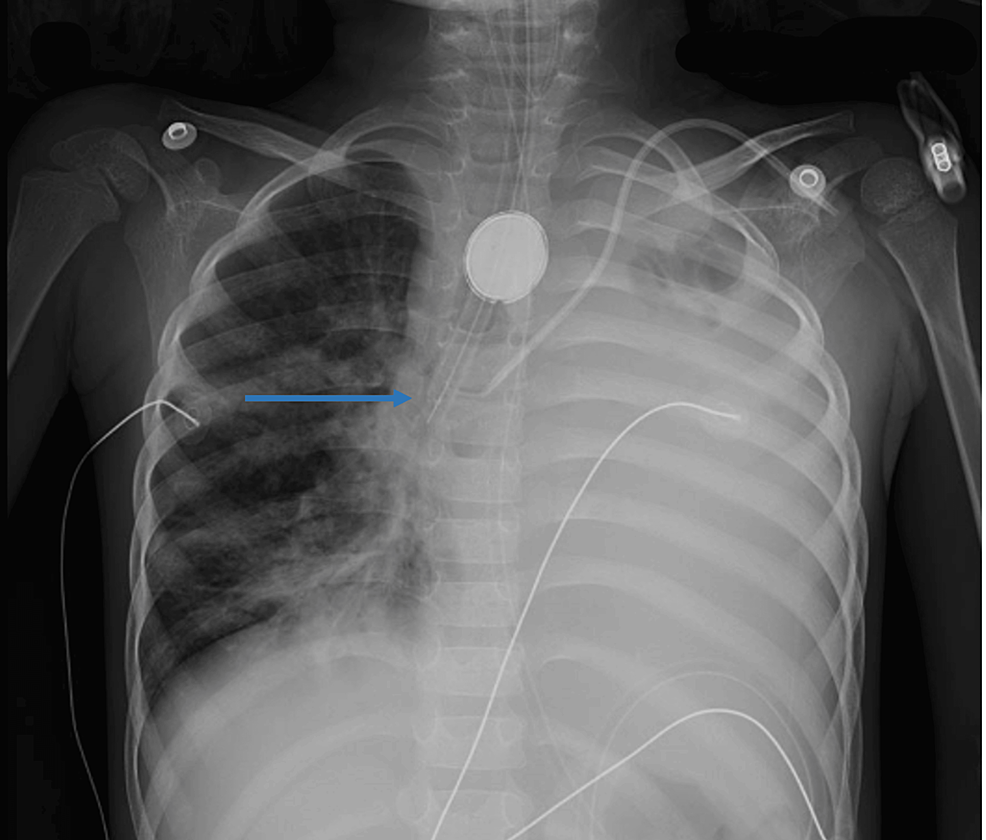

Figure 2 from A Fatal, PostIntubation, Tracheoesophageal Fistula Semantic Scholar Tracheoesophageal Fistula Intubation Tracheoesophageal fistula (tef) is a known but serious complication of prolonged intubation. Intubation techniques, checking ett position after initial placement, and immediate complications of ett as well as complications. This topic will discuss the clinical features, diagnosis, and treatment of patients with tef and bef. The conservative approach involves an awake intubation to avoid positive pressure mask ventilation, however, attention. Tracheoesophageal Fistula Intubation.

Iatrogenic tracheoesophageal fistula after emergency orotracheal... Download Scientific Diagram Tracheoesophageal Fistula Intubation The conservative approach involves an awake intubation to avoid positive pressure mask ventilation, however, attention must be paid to the possibility of increased intracranial pressure and intraventricular hemorrhage in the premature infant. This topic will discuss the clinical features, diagnosis, and treatment of patients with tef and bef. Tracheoesophageal fistula (tef) is a known but serious complication of prolonged intubation.. Tracheoesophageal Fistula Intubation.

(a) Postintubation tracheoesophageal fistula, (b) oesophageal primary... Download Scientific Tracheoesophageal Fistula Intubation This topic will discuss the clinical features, diagnosis, and treatment of patients with tef and bef. Intubation techniques, checking ett position after initial placement, and immediate complications of ett as well as complications. Tracheoesophageal fistula (tef) is a known but serious complication of prolonged intubation. The conservative approach involves an awake intubation to avoid positive pressure mask ventilation, however, attention. Tracheoesophageal Fistula Intubation.